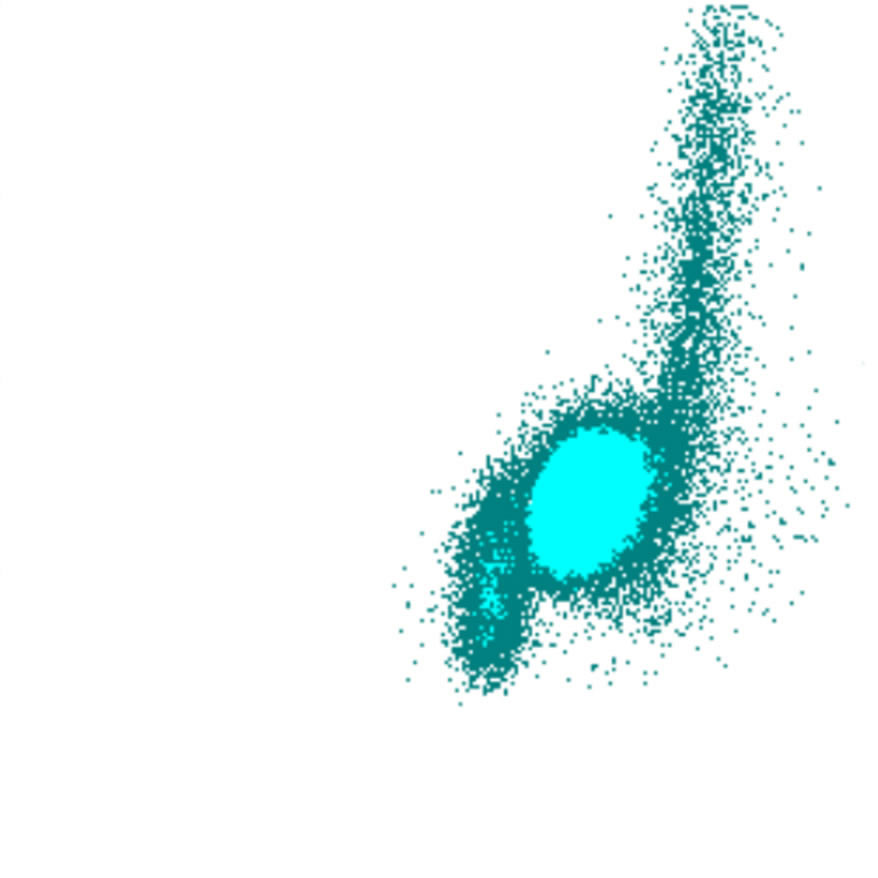

Side Fluorescence

Le signal SFL reflète la teneur en acides nucléiques des cellules. Les cellules avec un SFL élevé contiennent davantage d’ARN et/ou d’ADN, ce qui indique souvent une activité ou une prolifération accrue. Il existe une corrélation limitée entre le SFL et le FSC ; bien que les cellules plus grandes présentent généralement un SFL plus élevé, des exceptions existent, telles que des blastes avec un SFL relativement faible ou des lymphocytes activés avec un SFL élevé malgré leur plus petite taille.

SFL scatter

SFL faible

SFL élevé